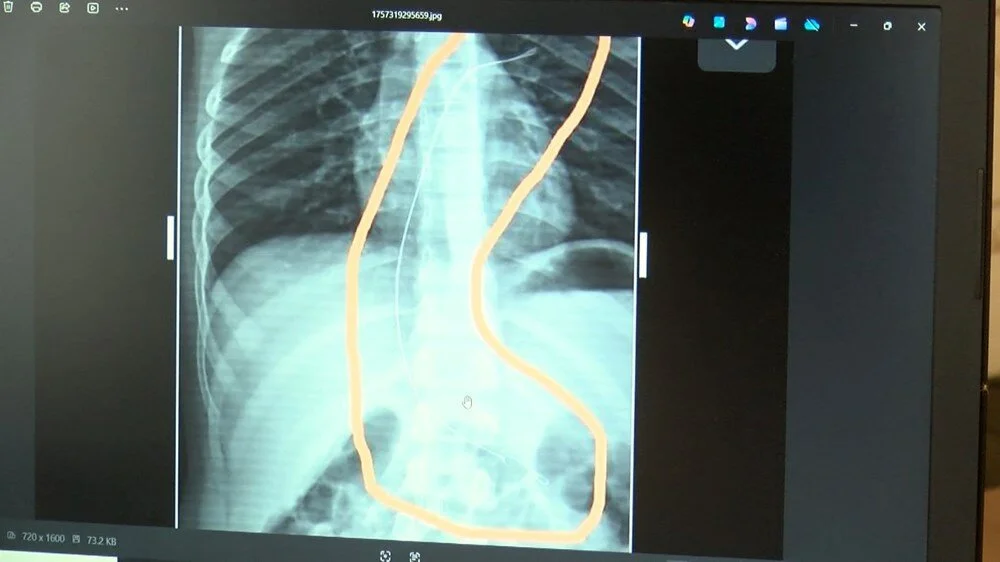

Burada çekilen röntgen ve MR'da Aram'ın vücudunda kateter unutulduğu görüldü.

Diyarbakır'daki Gazi Yaşargil Eğitim ve Araştırma Hastanesi Kadın Doğum ve Çocuk Ek Binası'na sevk edilen Aram, 5,5 saat süren riskli bir ameliyata alınarak 18 santimetre uzunluğundaki kateter çıkarıldı.

Gece saatlerinde çocuklarını hastaneye götürdüklerini anlatan anne, "Doktor röntgeni gösterdi. Tel kalmıştı. Çok kötü bir şekilde. Acil doktoru film çektikten sonra bize bir tel parçasını gösterdi. Bizi bekletmeden Diyarbakır’a sevkimizi verdiler." dedi.